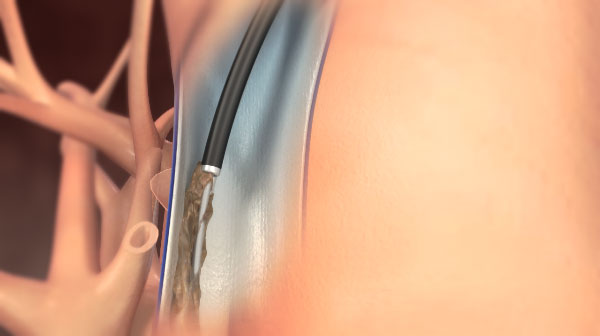

デバイス感染が起きると敗血症や感染性心内膜炎などを起こす恐れもあるため、リードを抜き取る必要があります。リードは植え込まれている年数が長い場合は、静脈や心臓の壁に癒着を起こし牽引しても抜けない状態になります。過度の牽引は血管損傷や穿孔といった致死的な合併症を引き起こす可能性が高く、開胸手術による摘出が行われていました。

エキシマレーザーシースによるリード抜去は、1997年FDAに認可されて以来、欧米にて急速に普及し高い成功率と安全性が報告されており、我が国においても2008年厚生労働省の認可を受け施行可能となり、施設基準があるものの2010年より保険適用となりました。